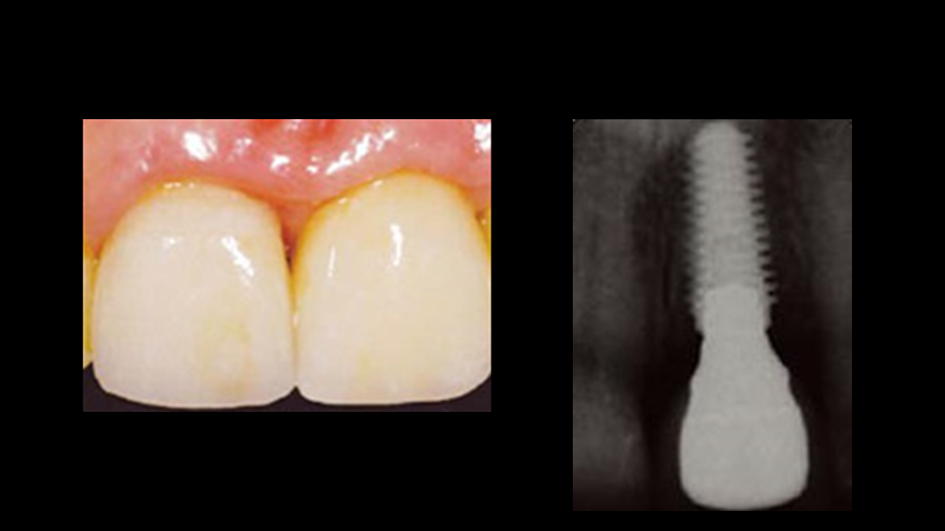

“Immediate loading of single AnyRidge implants

is a highly successful treatment modality. ”

Clinical case: Immediate post-extraction insertion of implant & immediate loading

- Courtesy of Prof. Giuseppe Luongo, Italy -

Keywords

AnyRidge, immediate loading, single implant, multicenter study, maxillary anterior, Prof. Giuseppe Luongo, single replacement

Products:

AnyRidge implant system

Reference

Immediate functional loading of single implants: a multicenter study with 4 years of follow-up

/J Dent Res Dent Clin Dent Prospect 2018; 12(1):26-37 | doi: 10.15171/joddd.2018.005

https://www.ncbi.nlm.nih.gov/pubmed/29732018